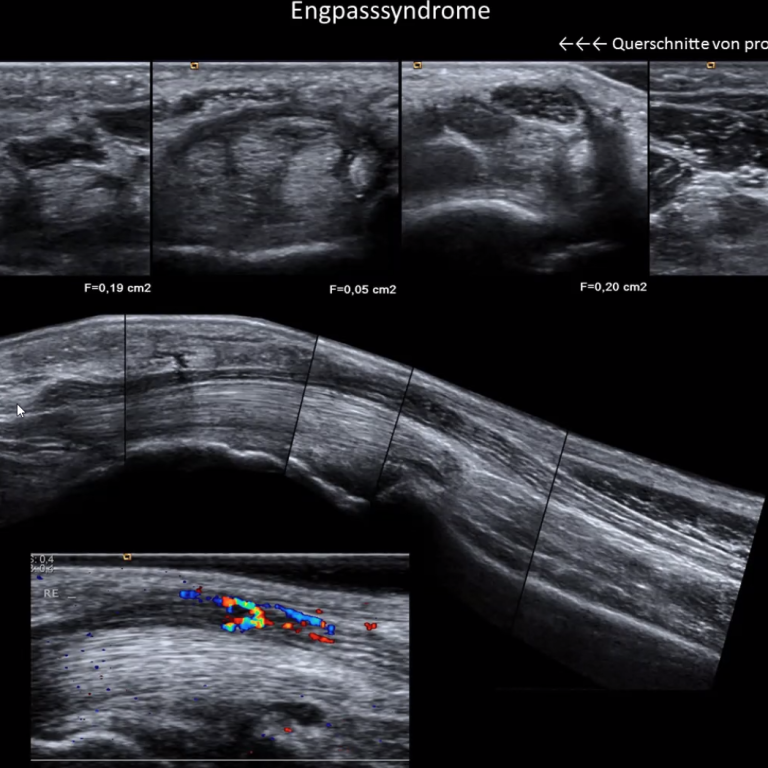

• Duplexsonografische Untersuchungen

Einsatz von fortschrittlichen Technologien in der Sonografie und Elektrophysiologie.